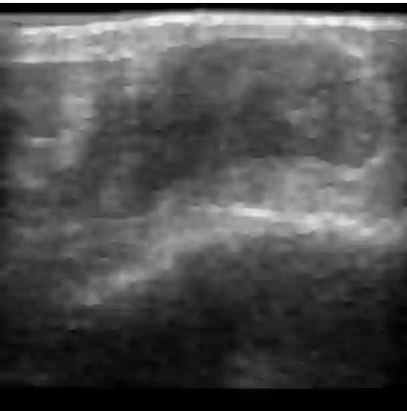

Chronic wounds including diabetic and arterial/venous insufficiency injuries have become a major burden for healthcare systems worldwide. Demographic changes suggest that wound care will play an even bigger role in the coming decades. Predicting and monitoring response to therapy in wound care is currently largely based on visual inspection with little information on the underlying tissue. Thus, there is an urgent unmet need for innovative approaches that facilitate personalized diagnostics and treatments at the point-of-care. It has been recently shown that ultrasound imaging can monitor response to therapy in wound care, but this work required onerous manual image annotations. In this study, we present initial results of a deep learning-based automatic segmentation of cross-sectional wound size in ultrasound images and identify requirements and challenges for future research on this application. Evaluation of the segmentation results underscores the potential of the proposed deep learning approach to complement non-invasive imaging with Dice scores of 0.34 (U-Net, FCN) and 0.27 (ResNet-U-Net) but also highlights the need for improving robustness further. We conclude that deep learning-supported analysis of non-invasive ultrasound images is a promising area of research to automatically extract cross-sectional wound size and depth information with potential value in monitoring response to therapy.